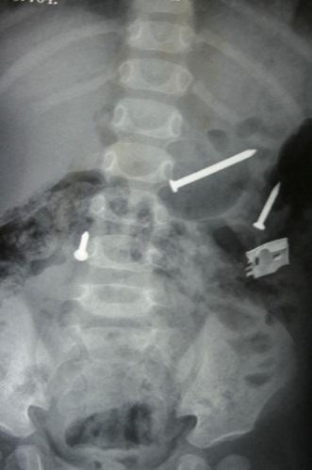

8241488971580176030.jpg

中國合肥的一位建筑工人從腳手架上摔下,導致一根鋼筋刺穿他的身體。